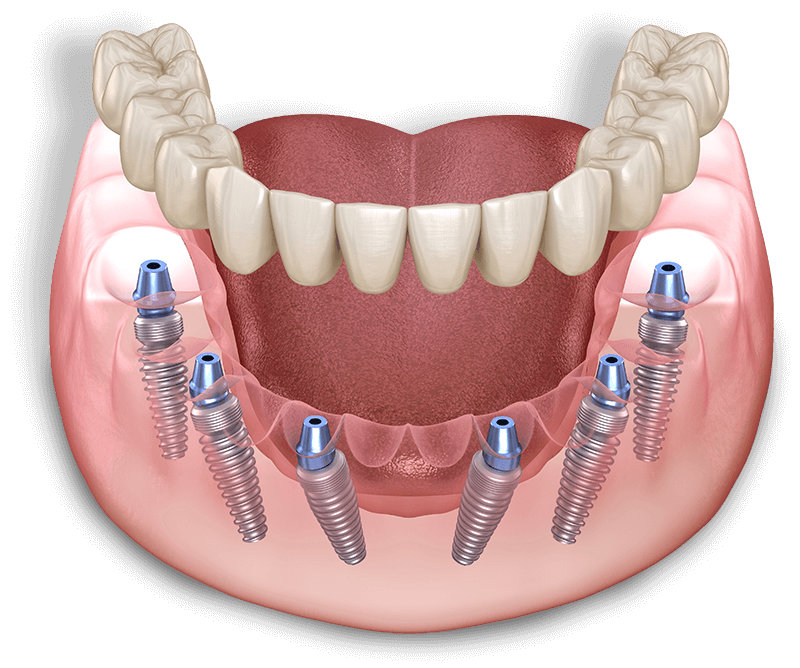

Full Arch Fixed Teeth

For patients missing many teeth, implant-supported overdentures offer a secure, affordable alternative to traditional dentures. Anchored on 2–4 implants, they stay firmly in place, resist slipping, and help preserve bone health. This solution improves comfort, enhances speech, and allows you to eat, chew, and taste food naturally. Reliable, stable, and confidence-boosting.